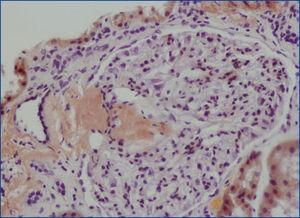

Se decide realizar una biopsia renal, que muestra 26 glomérulos, de los cuales 17 están esclerosados. En algunos de los glomérulos no esclerosados se observan muy focales depósitos nodulares de material hialino eosinófilo, acelular y débilmente ácido peryodico (PAS+) más frecuente en el polo vascular (figura 1), material que se observa también y en mayor cantidad en intersticio y en pared de arterias y arteriolas (figura 2). Este material se tiñe con la técnica de rojo congo (figura 3 y figura 4), tinción que desaparece tras el tratamiento con permanganato, y muestra birrefringencia verde manzana con luz polarizada. Con técnicas de inmunohistoquímica, el material acelular muestra tinción con amiloide A (figura 5). Se observa además una fibrosis intersticial y atrofia tubular moderadas (20 %). Con estos datos histológicos, se realiza el diagnóstico de amiloidosis renal secundaria (AA) con afectación glomerular, vascular e intersticial.

La amiloidosis se define por la acumulación extracelular de una proteína que muestra positividad con la técnica de rojo congo, birrefringencia verde manzana con luz polarizada y que en el estudio ultraestructural forma fibrillas de 10 nm no ramificadas y dispuestas de forma aleatoria. El material amiloide puede estar compuesto por una variedad de diferentes polipéptidos, que incluye cadenas ligeras de inmunoglobulinas (AL amiloide), cadenas pesadas (AH amiloide) proteína A amiloide (AA amiloide), beta-2-microglobulina, transtiretina, procalcitonina, beta-amiloide proteína, cistatina C, etc. La amiloidosis AA o secundaria se asocia a diferentes tipos de entidades, como enfermedades autoinmunes crónicas y enfermedades infecciosas crónicas, pero también aparece como complicación de la fiebre mediterránea familiar y en los CAPS. Independientemente de la causa, el amiloide presenta siempre las mismas características histológicas y ultraestructurales6. En nuestro caso, la biopsia renal muestra las características típicas de una amiloidosis secundaria tipo AA con depósitos de material amiloide preferentemente a nivel vascular, pero también en glomérulos e intersticio, con birrefringencia verde manzana con luz polarizada y que se pierde tras el tratamiento con permanganato. La positividad con inmunohistoquímica para amiloide A confirma el diagnóstico.

Figura 3. Rojo congo en polo vascular glomerular.